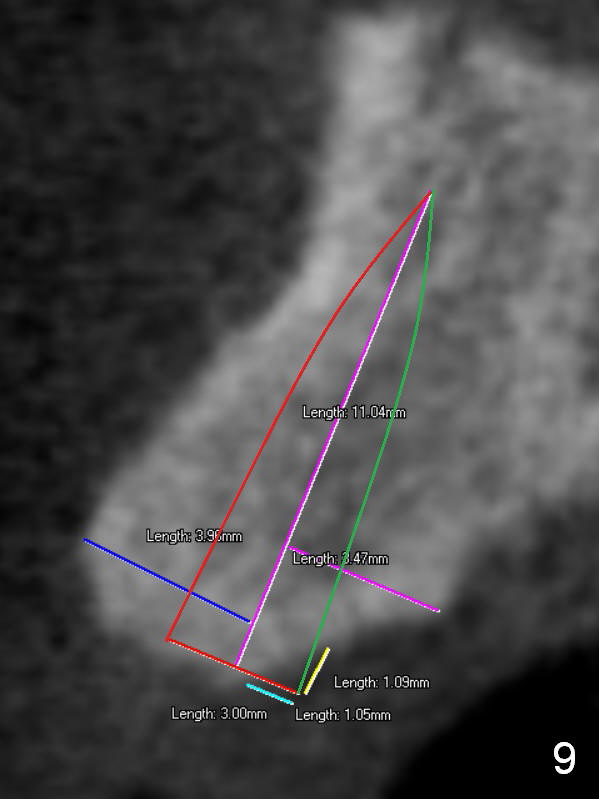

For the best trajectory, osteotomy at #8 should be initiated as palatally as possible (Fig.8 *). When a 4x11 mm 2-piece implant is placed, there is possibility that the apical buccal plate may be perforated (>). In contrast, a 3x11 mm 1-piece implant is more skinny with less coronal palatal thread exposure (Fig.9). The latter will be covered with bone graft and collagen dressing.

The second design is to place relatively smaller implants with the occlusion in mind (Fig.3,4). The starting point for the osteotomy will be as lingual as possible (especially Fig.4). The axis of the implant will be more parallel to the buccal plate. The angles of the angled abutments will be less (Fig.1 vs. 3; Fig.2 vs. 4). The cosmetic result may be better.

One piece implants (3 (angled or not, Fig.5) or 3.5 mm) may be tried (1,2,3). If SM (having gold coated abutment) or UF implants are selected, temporary abutments may be used for better adjustment of the gingival tissue around the provisional crowns.